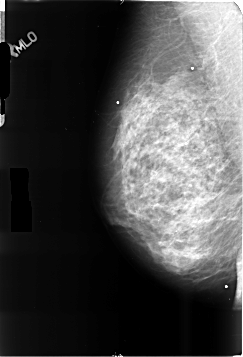

B_3500_1.RIGHT_MLO

RIGHT_MLO LINES 4640 PIXELS_PER_LINE 3152 BITS_PER_PIXEL 12 RESOLUTION 50 NON_OVERLAY